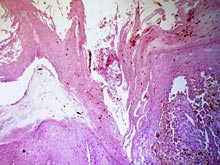

Манчестерский университет создал "тепловые гранаты", доставляющие противораковые лекарства прямо в опухоли. Попав внутрь, под действием тепла, вырабатываемого раковыми клетками, они взрываются, рассказывает "Vademecum". Комментирует Костас Костарелос, один из разработчиков метода: "В нашем случае тепловая "чека" установлена на температуре 42 градусов, что всего на пару градусов выше, чем нормальная температура тела. И, хотя мы проверили работу наших "гранат" пока только в лаборатории, существует целый ряд способов "нагреть" раковые клетки в организме пациентов, часть из которых уже используется в медицинской практике".

Основа "тепловых гранат" - липосомы. Это микроскопические структуры из клеточных мембран. Внутри у них скрываются молекулы лекарственного препарата. Итак, "гранаты", нагретые до определенной температуры, распадаются и выбрасывают лекарственное вещество прямо в клетки опухолей.

На сегодняшний день уже проведены эксперименты с культурами клеток злокачественных новообразований в лаборатории. Также стартовали доклинические испытания на животных. Ученым удалось уменьшить опухоли у животных и увеличить их выживаемость, кода в липосомах содержались антитела, способные распознавать клетки меланомы (одного из типов рака кожи).